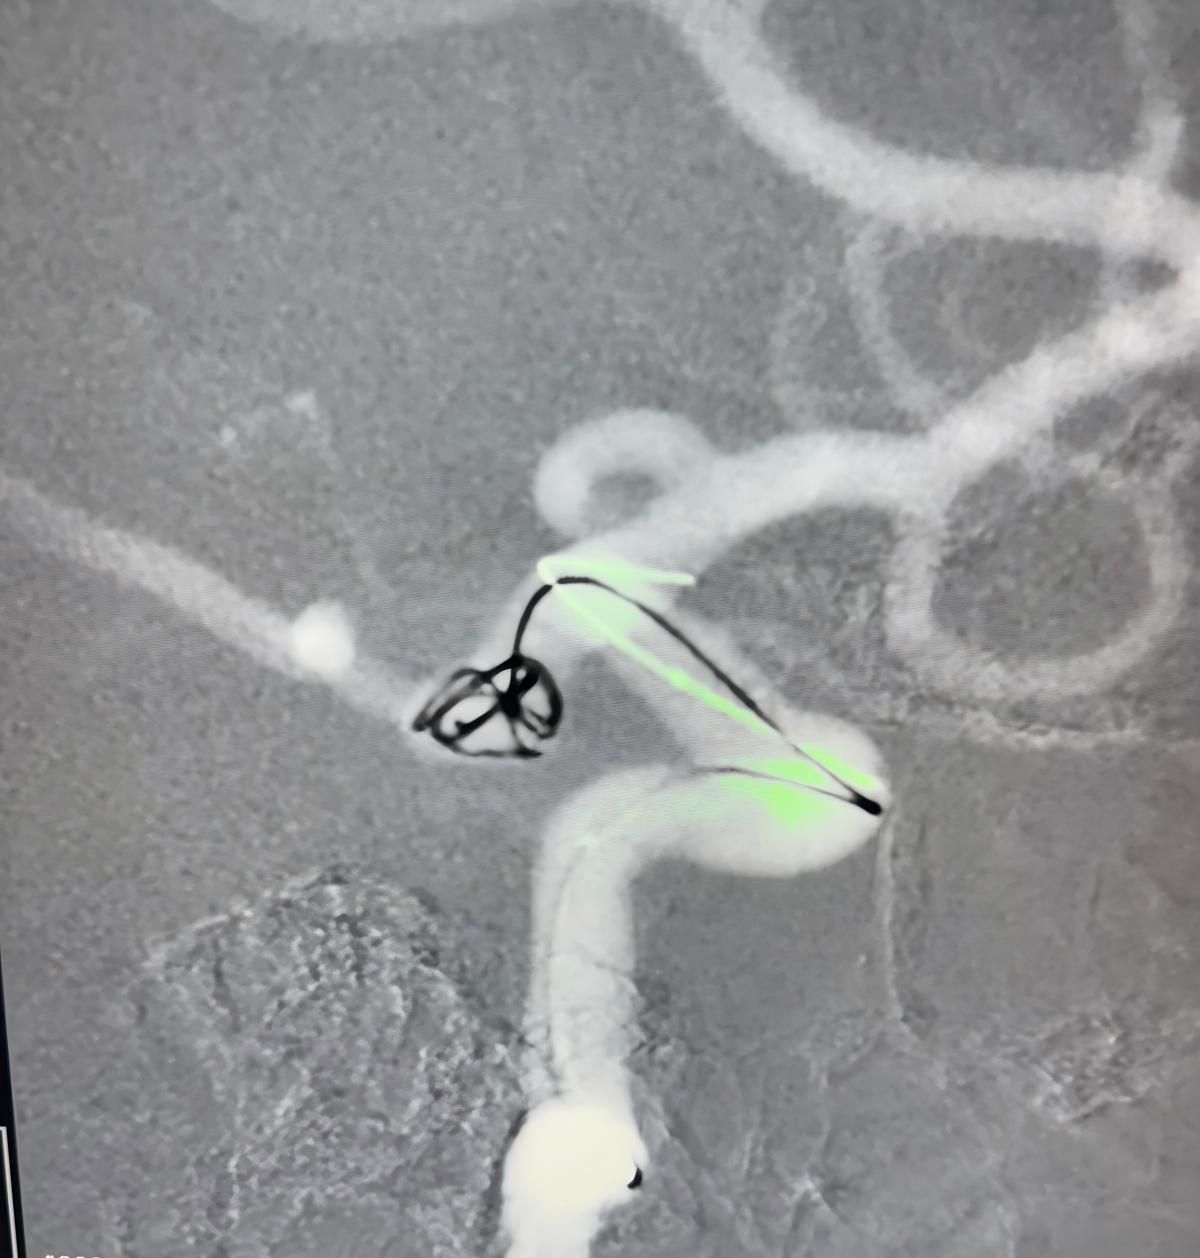

治療はNuvaを利用しました®流れのダイバーター (5.0-14 TJED-D) 、Perdenser®3Dコイル、およびFrepass®後部通信動脈動脈瘤用のマイクロカテーテル (TJMC18 Plus)。

Mutis博士は、デバイスの優れた視認性を強調し、回収がスムーズであると述べました。 彼は最終結果に大きな満足を表明した。